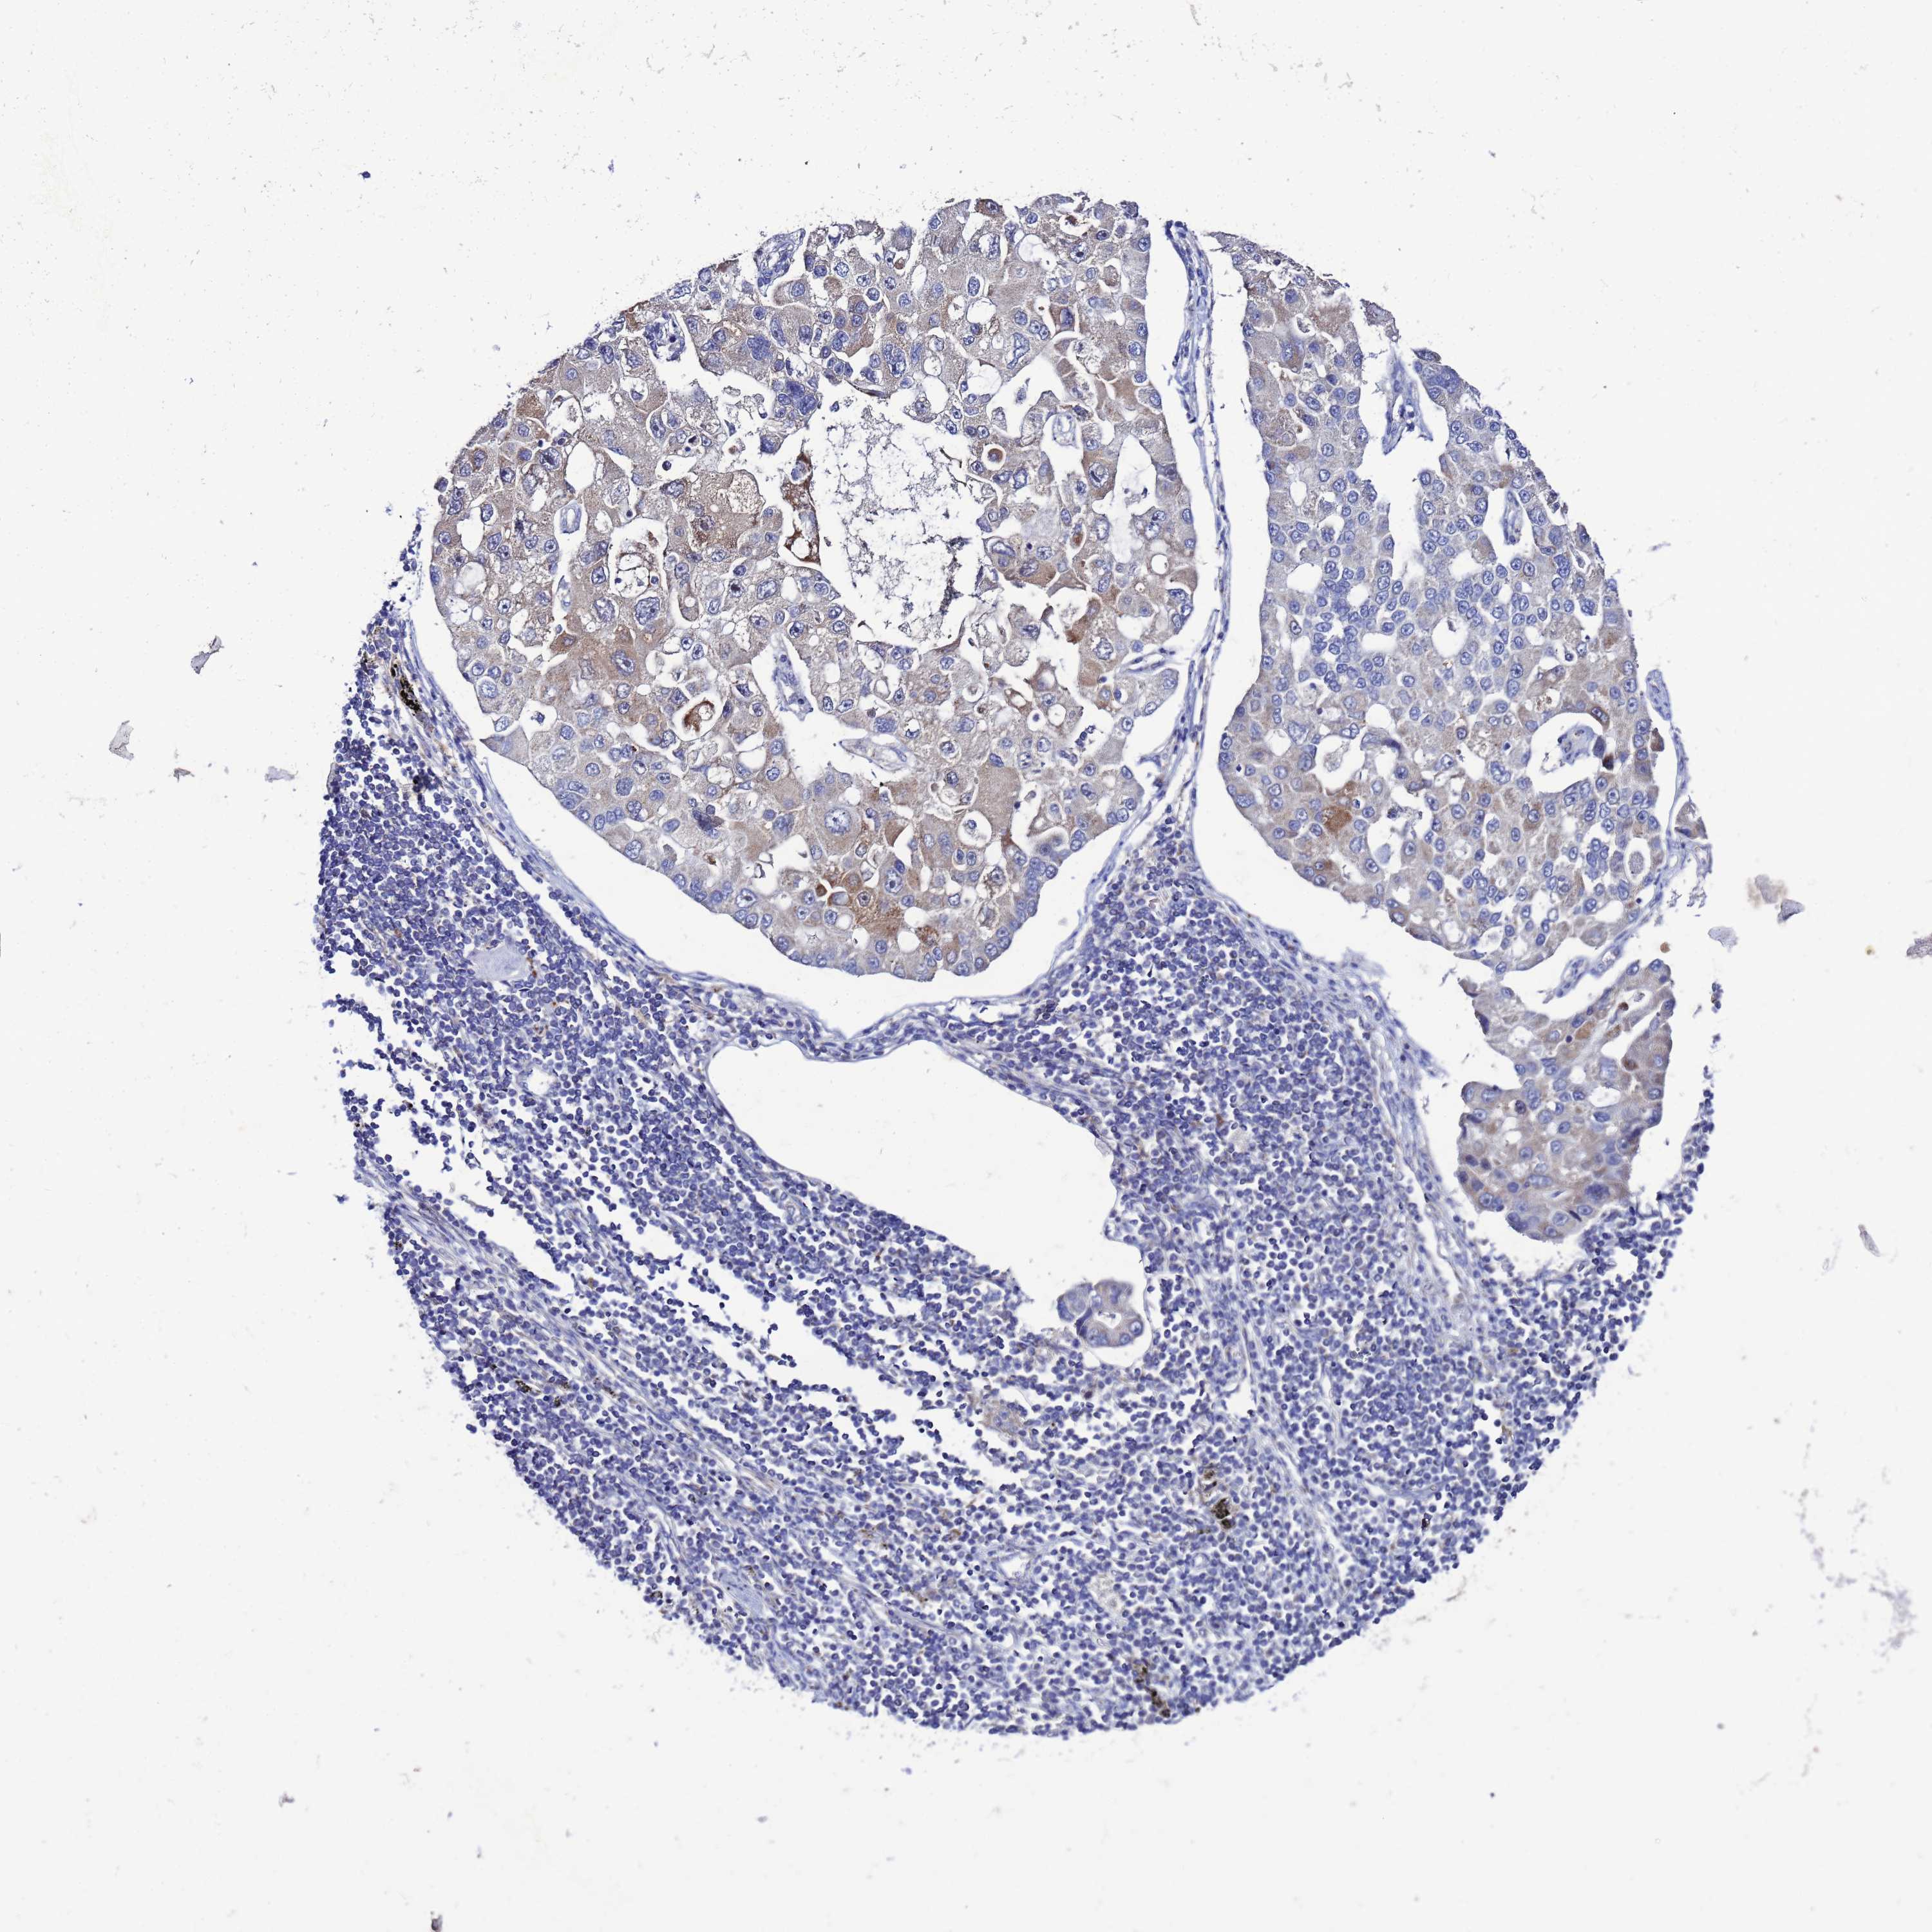

LUNG ADENOCARCINOMA (VALIDATION) - Interactive survival scatter ploti

The Survival Scatter plot shows the clinical status (i.e. dead or alive) for all individuals in the patient cohort, based on the same data that underlies the corresponding Kaplan-Meier plots. Patients that are alive at last time for follow-up are shown in blue and patients who have died during the study are shown in red.

The x-axis shows the expression levels (FPKM) of the investigated gene in the tumor tissue at the time of diagnosis. The y-axis shows the follow-up time after diagnosis (years). Both axes are complimented with kernel density curves demonstrating the data density over the axes. The top density plot shows the expression levels (FPKM) distribution among dead (red) and alive patients (blue). The right density plot shows the data density of the survived years of dead patients with high and low expression levels respectively, stratified using the cutoff indicated by the vertical dashed line through the Survival Scatter plot. This cutoff is automatically defined based on the FPKM cutoff that minimizes the p-score. The cutoff can be changed by dragging the vertical line or by entering a cutoff value in the square labeled "Current cut-off".

Under the Survival Scatter plot the p-score landscape (black curve; left axis) is shown together with dead median separation (red curve; right axis). Dead median separation is the difference in median mRNA expression between patients who have died with high and low expression, respectively. It is calculated as follows: median FPKM expression of dead patients with high expression - median FPKM expression of dead patients with low expression. This is intended to aid the user in visually exploring custom cutoffs and the associated p-scores and dead median separation.

Individual patient data is displayed and can be filtered by clicking on one or more of the category buttons on the top of the page. Categories describing expression level and patient information include: high, low, alive, dead, female, male and tumor stages. The scale of the x-axis can be toggled between linear and log-scale by clicking on the "x log" button. Mouse-over function shows TCGA ID, patient information and mRNA expression (FPKM) for each patient.

& Survival analysisi

Kaplan-Meier plots summarize results from analysis of correlation between mRNA expression level and patient survival. Patients were divided based on level of expression into one of the two groups "low" (under cut off) or "high" (over cut off). X-axis shows time for survival (years) and y-axis shows the probability of survival, where 1.0 corresponds to 100 percent.

FAHD2A is not prognostic in Lung Adenocarcinoma (validation)

Best expression cut offi

Based on the FPKM value of each gene, patients were classified into two groups and association between prognosis (survival) and gene expression (FPKM) was examined. The best expression cut-off refers the FPKM value that yields maximal difference with regard to survival between the two groups at the lowest log-rank P-value. Best expression cut-off was selected based on survival analysis .

When clicking on this number, the vertical dashed line indicating cut-off, the interactive survival plot, and the Kaplan-Meier curve will be adjusted to show results based on the best expression cut-off.

: 19.09

P scorei

Log-rank P value for Kaplan-Meier plot showing results from analysis of correlation between mRNA expression level and patient survival.

N/A

TCGA RNA samplesi

RNA-seq data is reported as average FPKM (number Fragments Per Kilobase of exon per Million reads), generated by the The Cancer Genome Atlas (TCGA) .

Normal distribution across the dataset is visualized with box plots, shown as median and 25th and 75th percentiles. Points are displayed as outliers if they are above or below 1.5 times the interquartile range. FPKM values of the individual samples are presented next to the box plot.

Average pTPM 16.7

Number of samples 105